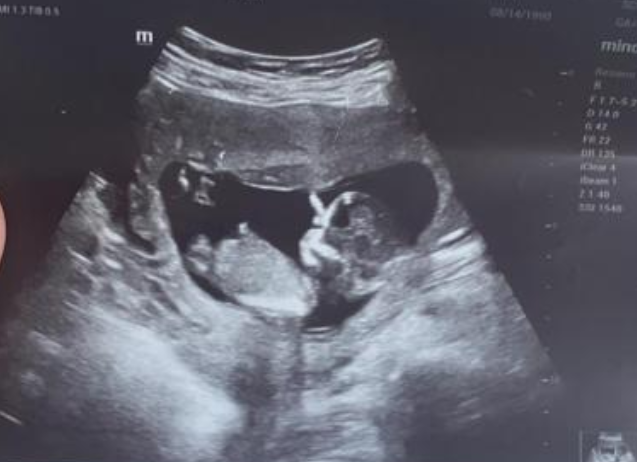

13周处于妊娠中期,此时B超可见胎儿发育成人形,主要用于颈项透明带、鼻骨的显示与测量和胎儿形态学的筛查等方面。

13周B超可见胎儿发育成人形,胎体自然屈曲,头顶及骶尾部清晰显示,躯干部显示脊柱矢状面全长。同时,显示颈后部皮下组织、皮肤、羊膜形成的三条强回声带。此时显示胎儿面部轮廓,鼻尖清晰。颅脑中部可见低回声的间脑,后方显示颈项透明层。胎儿鼻骨显示为三条强回声短线,上方近额骨强回声线为鼻梁皮肤回声,下方为鼻尖回声,鼻尖上方略偏高处的强回声线即为鼻骨回声。

13周B超检查主要用于进行颈项透明层、鼻骨的显示与测量,同时进行胎儿初步形态学的筛查。可通过测量胎儿头臀长较准确的推算出超声孕周,可为孕15-20周进行的产前筛查提供较可靠依据,其适应证包括年龄大于35岁的高危孕妇、既往有染色体异常胎儿病史或家族史、早孕期有病毒感染史或服用某些药物接触史、孕妇有胎儿发育异常史等。